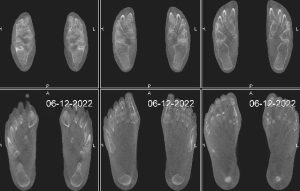

Il s’agit d’un appareil type cone beam permettant d’étudier en position débout, comme un scanner, les pieds, les chevilles et les genoux avec une très faible irradiation du patient comparé à un scanner conventionnel.

Il se destine aux pathologies liées aux troubles posturaux, aux douleurs des avants et arrières pieds.

Sa finesse d’image lui permet aussi d’être au cœur des bilans traumatiques et rhumatismaux de la cheville et du coup de pied.

Il suffit de moins d’une minute pour obtenir une acquisition volumique 3D des pieds et des chevilles.